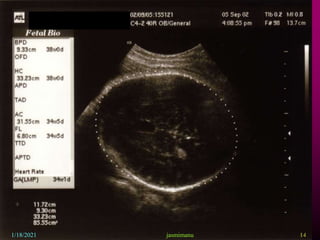

This document provides information about intrauterine growth restriction (IUGR), including its definition, classification, etiology, diagnosis, treatment and risks. IUGR occurs when a baby's growth is slowed or restricted during pregnancy. It can be symmetric, affecting overall growth, or asymmetric, affecting the growth of some parts more than others. The causes of IUGR are often unknown but can include maternal, fetal, placental or genetic factors. Diagnosis involves assessing growth via ultrasound and monitoring blood flow. Treatment may involve bed rest, aspirin or early delivery depending on gestational age and fetal wellbeing. Both short and long term risks to the infant are increased with IUGR.